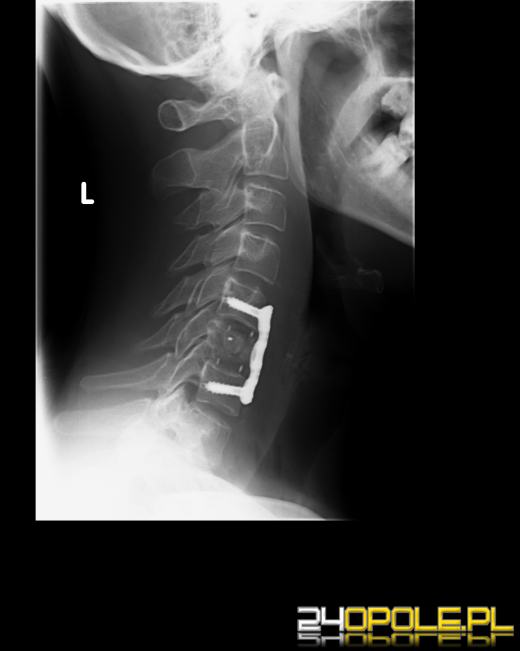

Od początku wakacji prawie nie ma dnia, by na izbie przyjęć nie pojawił się choć jeden amator skoków do wody. Czasem kończy się na skręceniu czy stłuczeniu kręgów szyjnych - wtedy można mówić o szczęściu. Gorzej, gdy kręgosłup wymaga operacji. Oznacza to, że w najlepszym przypadku poleżymy kilka tygodni w szpitalu, a w naszym kręgosłupie lekarze zamontują usztywniające blaszki. Najgorszy wariant to ten, gdy dojdzie do przerwania rdzenia kręgowego. Wtedy następuje paraliż części ciała i brak kontroli nad czynnościami fizjologicznymi.